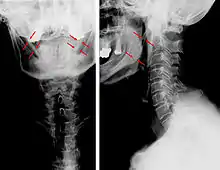

| Anteroposterior and lateral radiographs of cervical spine showing ossification of the stylohyoid ligament on both sides | |